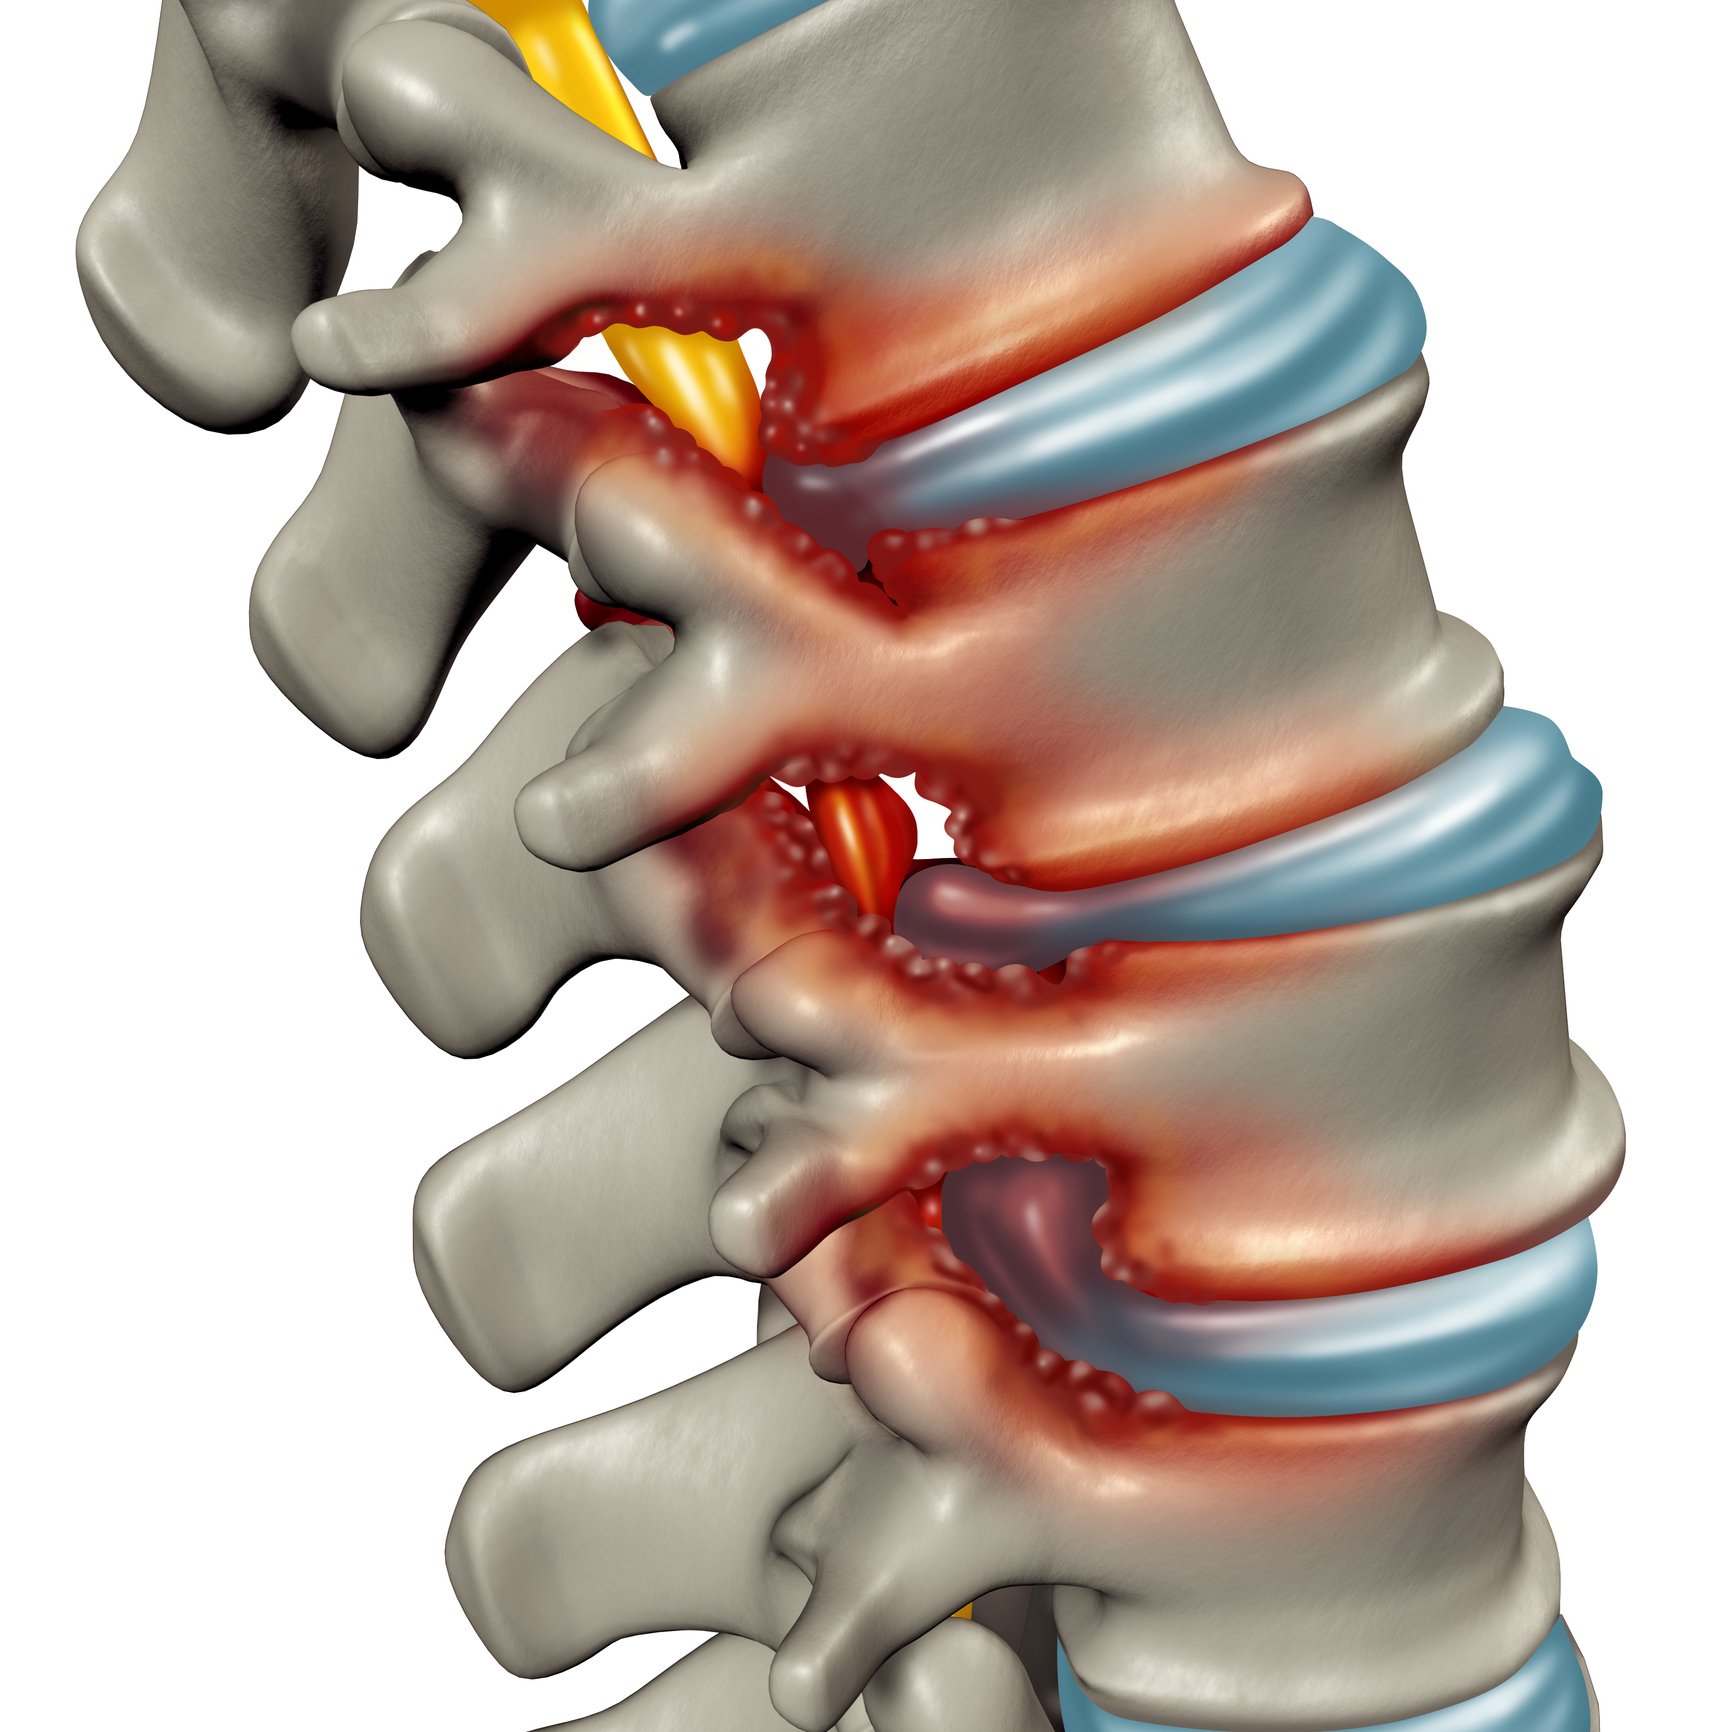

Herniated Disk in the Lower Back – OrthoInfo – AAOS

slipped disc quick fix – Nathan Cornish

What is a spinal disc bulge or herniation? – DR. JASON ADAMS B.HSC, D.C …